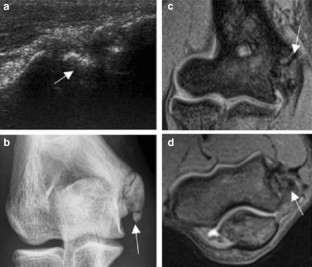

Fig. 2